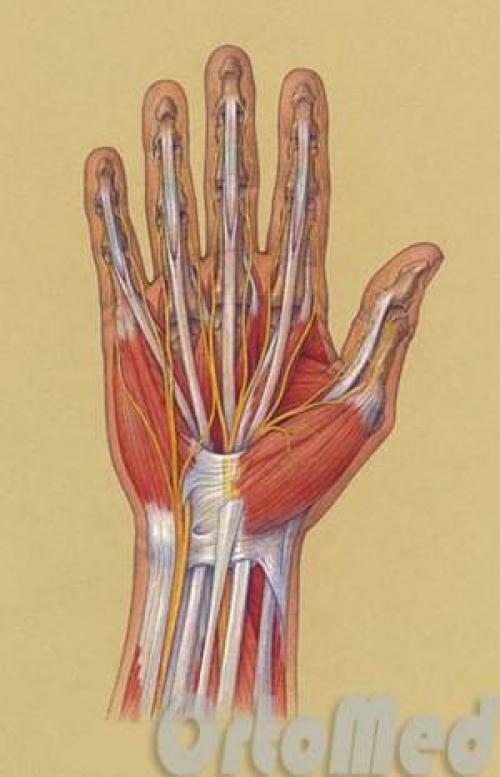

Анатомия кисти сухожилия. Анатомия сухожилий сгибателей

Сухожилия сгибателей делятся на поверхностные и глубокие. Сухожилия поверхностных сгибателей прикрепляются к средним фалангам, а сухожилия глубоких сгибателей – к дистальным (ногтевым). Все сухожилия расположены в каналах, в которых они скользят. Когда мышцы сокращаются, сухожилия тянут за собой соответствующие фаланги и происходит сгибание пальцев. Эти мышцы расположены на предплечье.

Сухожилия на тыльной стороне кисти и предплечья известны как сухожилия разгибателей.

Сухожилия сгибателей удерживаются в каналах кольцевидными связками. Это обусловливает плавное сгибание без натяжения кожи.

Сухожилия можно очень легко повредить ввиду того, что они расположены очень близко к поверхности кожи. И довольно неглубокая рана кисти, скорее всего, будет с повреждением сухожилий сгибателей.

Так как нервы, сосуды на кисти и предплечье находятся рядом с сухожилиями, неглубокое ранение может привести к их повреждению. Повреждение нерва приведет к онемение на одной или обеих сторонах пальца, но повреждение обеих пальцевых артерии приведет к более серьезным последствиям - резкой ишемии пальца (отсутствие кровоснабжения), что может стать причиной некроза пальца. Это требует, конечно, немедленной операции – реваскуляризации пальца (сшивание сосудов).